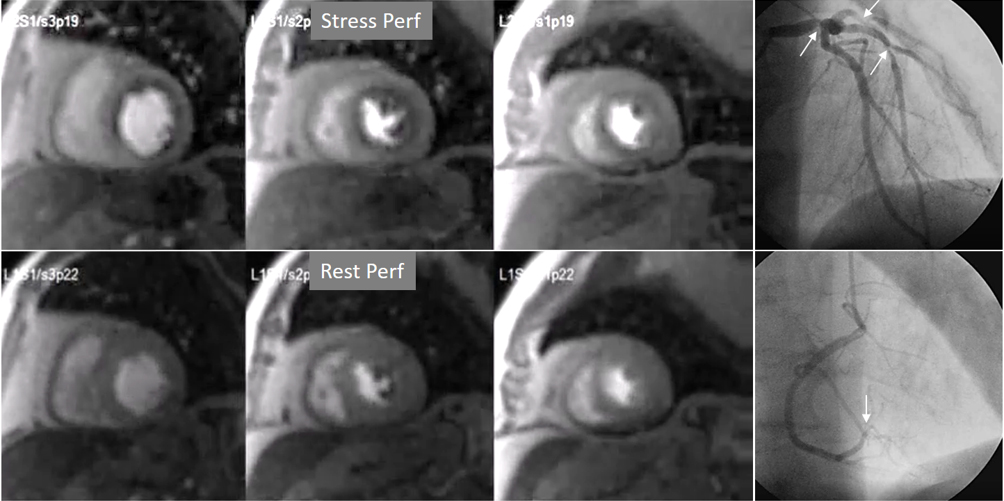

The most immediate and commonest method of analysis is the visual detection of a distinctive deficient increase in signal intensity of a region of the left ventricular myocardium during the first passage of a CA bolus under vasodilatory conditions lasting for at least 3 consecutive frames of the sequence. This perfusion defect should not be present at rest and should not correspond to an area of previous MI. The detection of such a defect is assumed to be due to a reduction in CFR of this territory which, when attributed to a particular coronary artery [39], allows for the conclusion of the presence of a significant epicardial stenosis in the vessel (Fig. 6).

Fig. 6.Single-vessel perfusion defect. Extensive subendocardial perfusion defect at the antero-septal region (arrow, on the upper left panel) not present at rest, in a region without LGE (lower left panel). Angiography proves this defect to be due to a tight stenosis of the LAD coronary artery (arrow, on the lower right panel).

Criteria for an appropriate interpretation of dark, unenhanced regional myocardial signals as due to perfusion defects have been issued by scientific societies [40]. According to these recommendations, it is accepted that a true defect (1) appears when contrast arrives at the left ventricular myocardium, (2) persists for several cardiac cycles, (3) is not restricted to a thin linear contour, (4) it is more prominent at the subendocardial level, extending variably through the whole thickness of the myocardium, (5) it is not present at rest, and (6) corresponds to a distribution territory of a coronary artery.